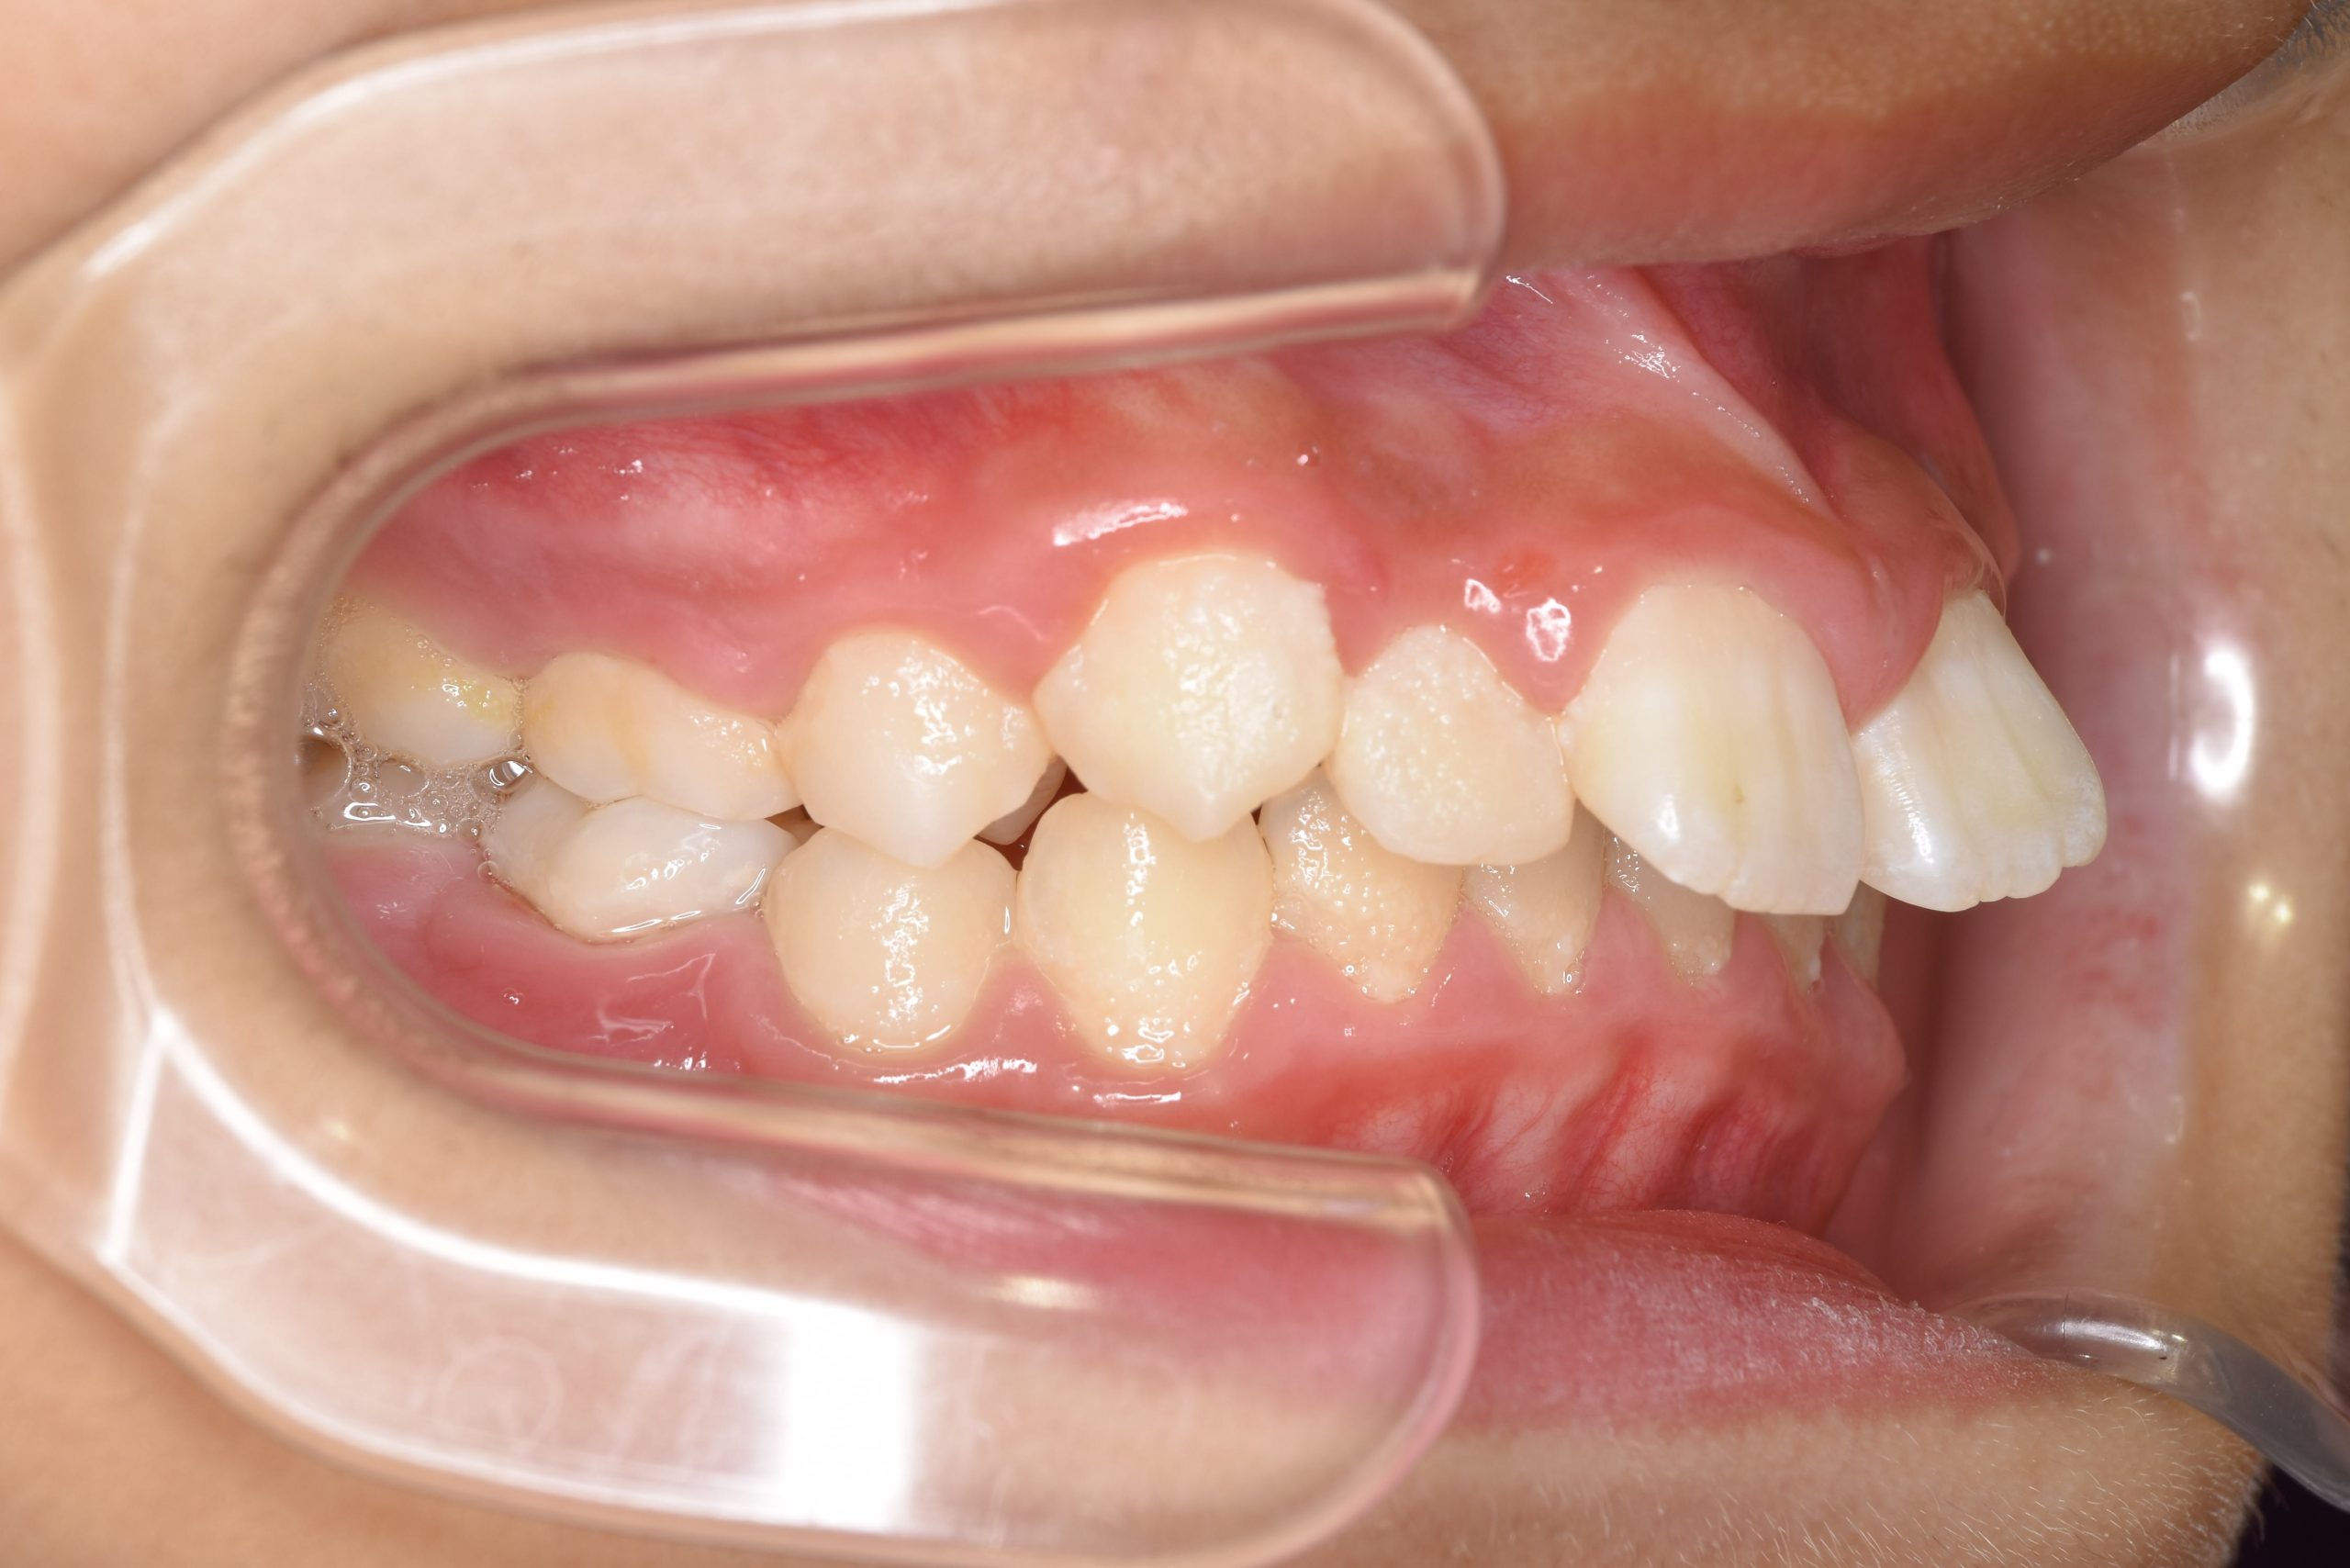

全顎ワイヤー矯正 症例_218 Case

ビフォー

主訴 出っ歯|歯の隙間

施術内容 小児矯正1期治療

治癒期間 1年11ヶ月間

費用 465,400円(税込)

リスク・副作用 違和感、不快感、痛み